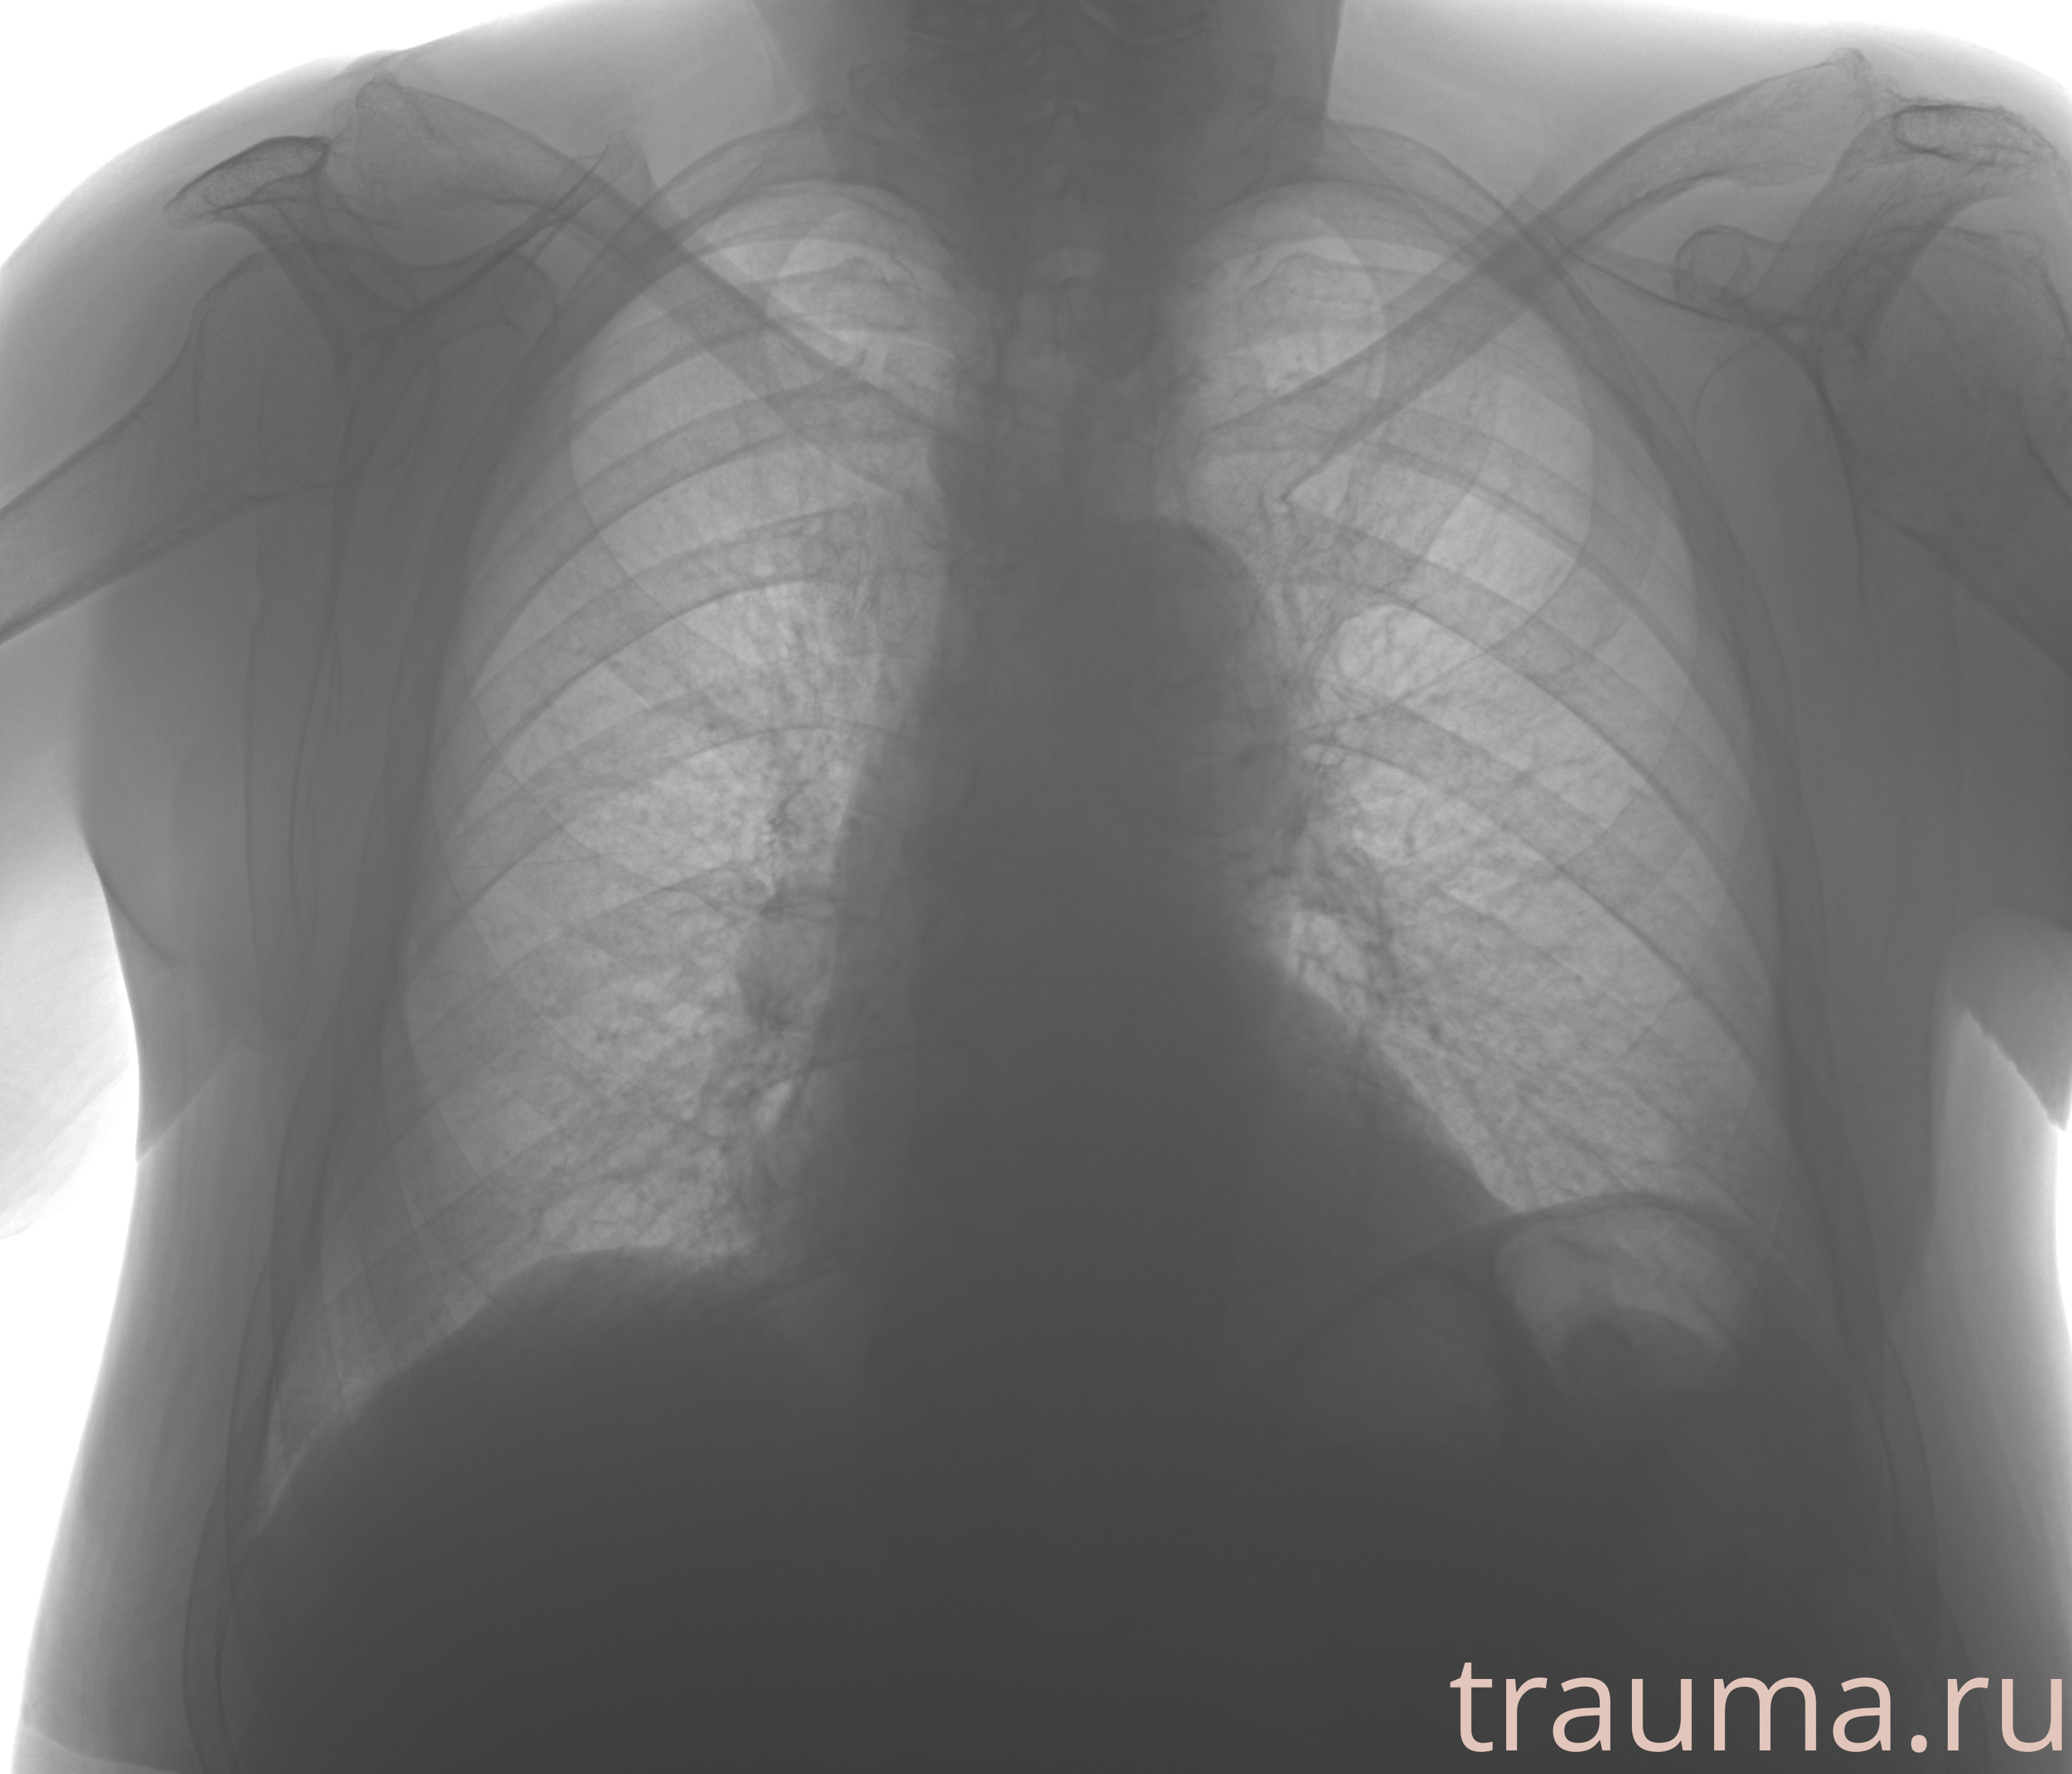

Рентген на дому: по вашему адресу приезжает врач-рентгенолог, травматолог-ортопед с мобильным рентгеновским аппаратом, проводит диагностику травмы или заболевания, делает необходимые рентгенограммы, дает рекомендации по дальнейшему лечению. Получить качественные снимки в домашних условиях возможно благодаря уникальной методике, разработанной МосРентген Центром для института  Склифосовского

при переломе шейки бедра и пневмонии от компании МосРентген Центр - партнера Института имени Склифосовского